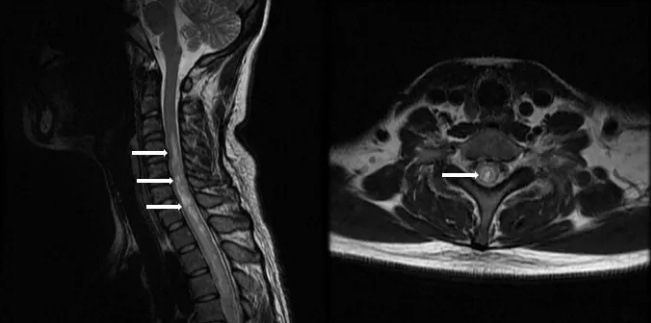

NMOSD患者MRI检查显示脊髓病变(箭头所示)